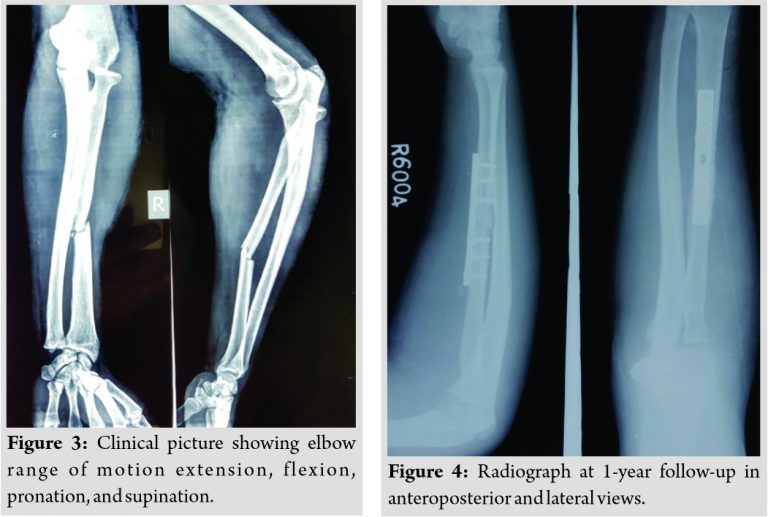

Postoperatively, the limb was immobilized in a splint at 90 of flexion and 45 of pronation. The radiocapitellar wire was removed at 3 weeks; then, he was started on gentle range of motion exercises after k-wire removal. At 6 months follow-up, range of motion of the elbow was 30 of extension to 120 of flexion and near-normal forearm pronation of 70 and supination of 60 (Fig. 3). On examination, he had no pain over the right forearm and his wounds were healed. At his last visit, 1 year after the operation, he had excellent range of motion with no major complaints. Radiographs showed that the fracture was healed in good alignment and the radiocapitellar joint remained reduced (Fig. 4).The patient reported no pain and was able to resume his normal daily activities, including working as a pharmacist.